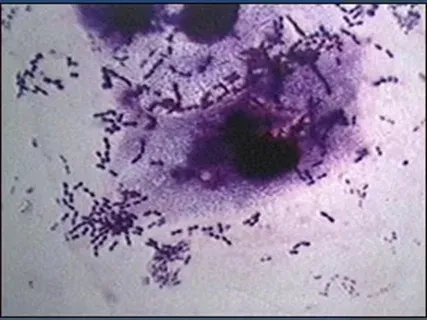

Pneumococcal disease in humans image